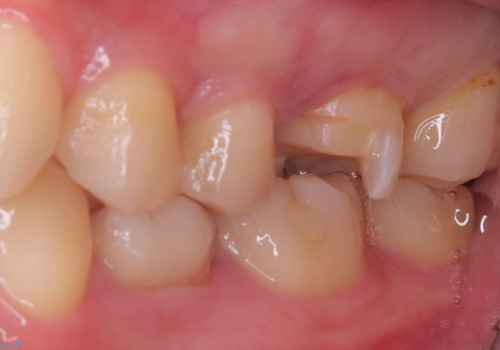

- 主訴:右上6番目の歯が黒ずんで見える。

右上6番に保険適用の歯冠色材料を使ったインレーが入っていましたが、歯質とインレーとの境目に不適部位が存在しそこから二次う蝕になっていました。

セラミックインレーでのやり替えを提案し、また残存歯質量と破折のリスクを説明し、アンレー形態となりました。